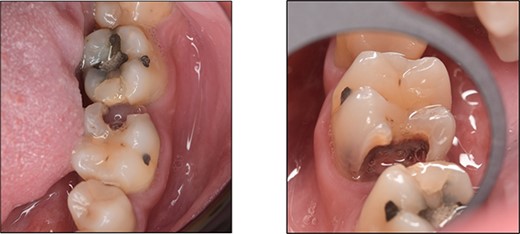

A 44-year-old patient presented to our clinic with the primary complaint of food lodgment in a cavity on the lower left posterior teeth. Clinical examination revealed extensive caries on the disto-occlusal surface of the lower left first permanent molar (tooth 36) (Fig. 1). Radiographic examination showed a large radiolucency at the distal crown extending to the cervical third of the distal root, with periapical radiolucencies on both mesial and distal roots (Fig. 2). The tooth was diagnosed with asymptomatic irreversible pulpitis and symptomatic apical periodontitis.

Clinical photograph of tooth 36 showing extensive caries on disto-occlusal surface.

Periapical radiograph of tooth 36 showing a large radiolucency area at the distal crown involving the cervical third of the distal root.